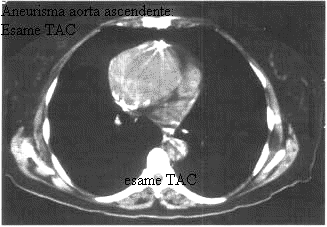

TC e RM

Sono metodiche sicuramente appropriate nella diagnostica degli aneurismi toracici e toracoaddominali.

La TC tradizionale è la tecnica più sensibile nell'individuazione di lesioni con componenti calcifiche. Il suo limite, in passato, era determinato dalla impossibilità di distinguere i falsi aneurismi da quelli veri, e tale ostacolo è stato superato dall'introduzione dell'ANGIO-TC in cui si utilizza un mezzo di contrasto.

Le immagini TAC forniscono informazioni dettagliate sulla sede, morfologia, dimensioni dell'aneurisma, sulla eventuale presenza di calcificazioni e trombi endoaneurismatici; permettono inoltre di cogliere i rapporti tra la sacca aneurismatica e le strutture anatomiche ad essa contigue oltre che, in caso di rottura, la sede dello stravaso ematico.

La TC spirale riesce ad ottenere una visione panoramica angiografica multiplanare o tridimensionale dell'aorta o delle arterie iliache e ciò permette una valutazione più precisa del diametro dell'aneurisma e dell'estensione del colletto aneurismatico, sede dell'eventuale clampaggio aortico. La possibilità di eseguire scansioni più sottili, con il massimo effetto contrastografico arterioso, permette inoltre una migliore valutazione dei rapporti con le maggiori branche arteriose rispetto alla TC tradizionale.